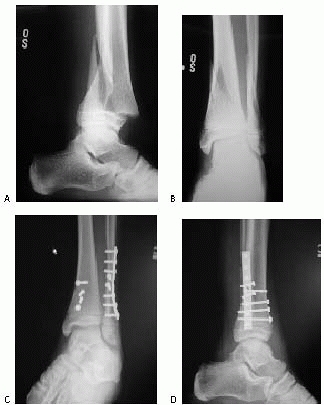

![]() |

FIGURE 26-33 A. Severely displaced pronation-eversion-external rotation injury. B.

Closed reduction was unsuccessful, and a valgus tilt of the ankle mortise was noted. At surgery, soft tissue was interposed laterally (arrows). C. Reduction completed and stabilized with two cancellous screws placed above the physis. |